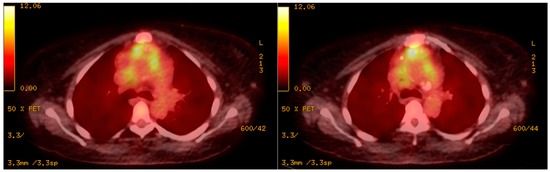

2. Case Presentation